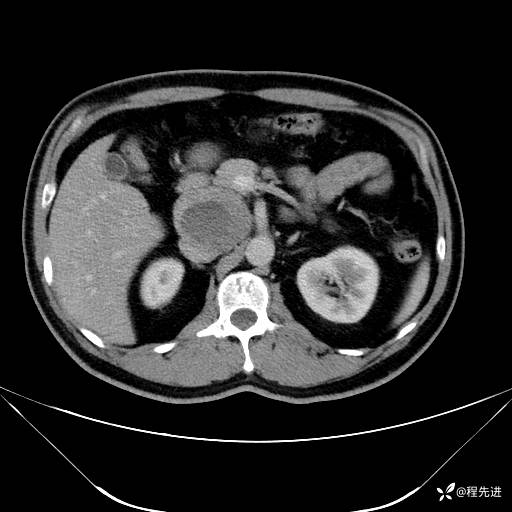

【腹盆】特别精彩病例|发现腹膜后肿物1月余

主诉:发现腹膜后肿物1月余

现病史:患者1月余前查体,行超声检查提示:后腹膜囊实性肿块;慢性胆囊炎伴胆囊内结石;无腹痛腹胀,不伴腹泻发热等;偶感腰背部酸痛。

CT平扫+增强: